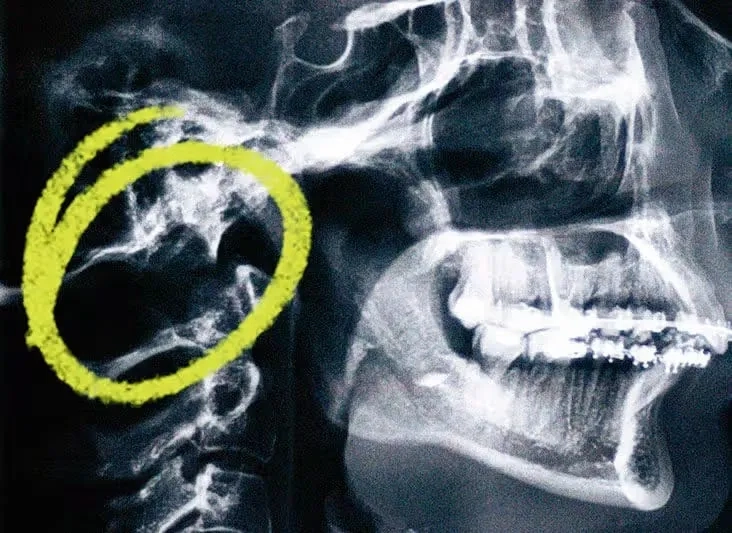

Decompression surgery for Chiari malformation